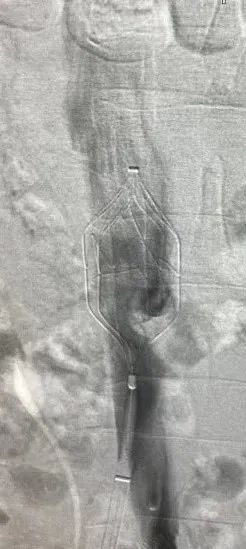

▲造影血栓保护装置

拦截到血栓